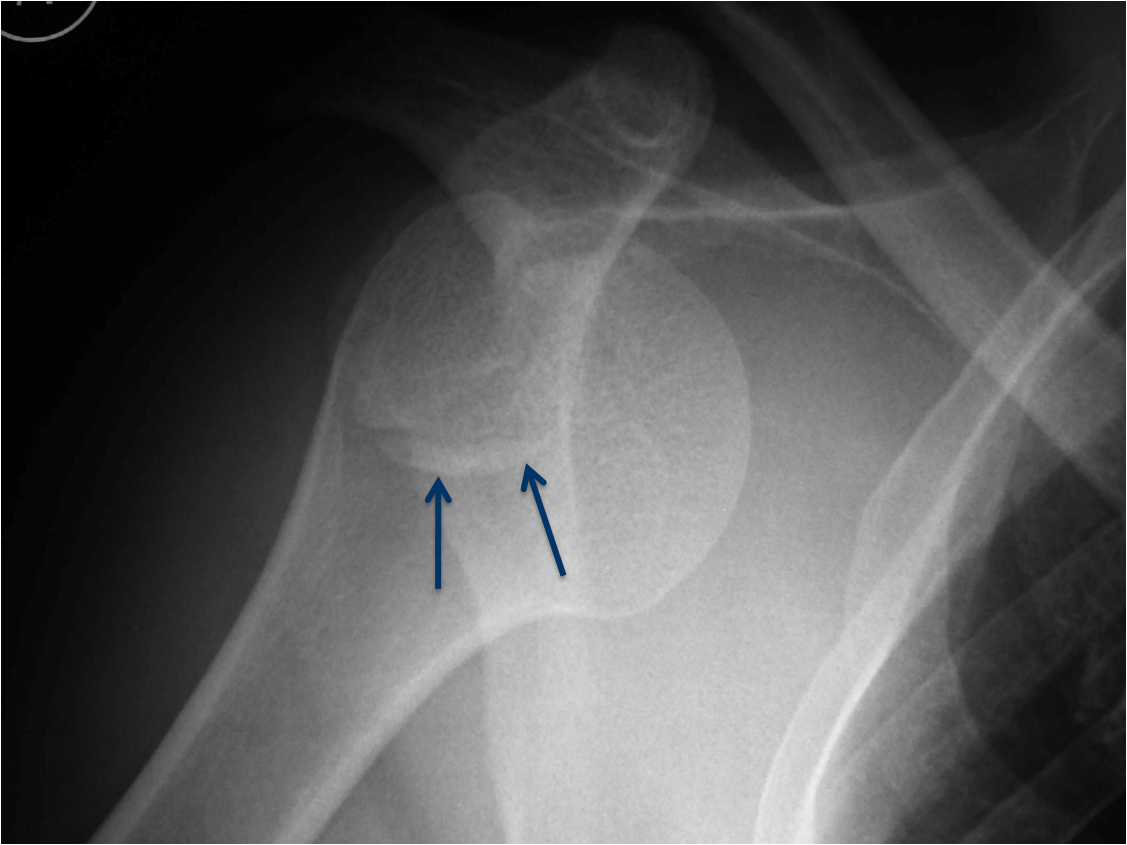

This is an example of a patient with an anterior shoulder dislocation. The bony Bankart lesion can be seen (arrows).